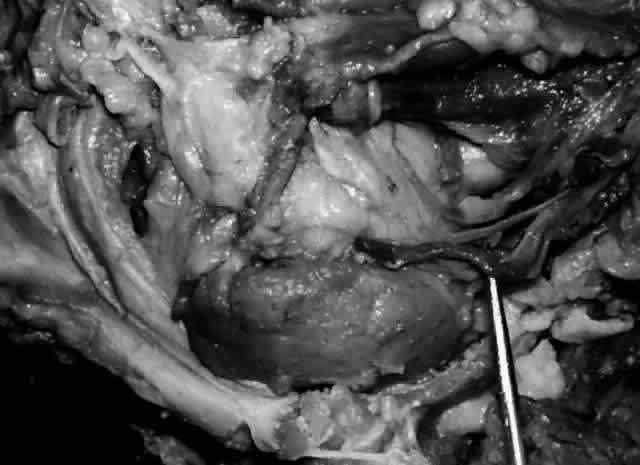

The main lacrimal gland resides in the superotemporal orbit, partially within a shallow bony fossa in the lateral angular process of the frontal bone (fossa glandula lacrimalis). The gland is situated between the eyeball below and the curved orbital wall above, giving it a somewhat compressed and curved shape. It may extend inferiorly to the lateral canthal tendon. The lateral horn of the levator aponeurosis crosses the gland anteriorly, separating it into a larger superior or orbital lobe and a smaller inferior or palpebral lobe (Fig. 2). The division is incomplete because the larger orbital lobe is connected to the smaller palpebral lobe posteriorly by a bridge of glandular tissue, draining tubules, and Müller's muscle, which is attached to the underside of the levator muscle and aponeurosis. The lacrimal gland is surrounded by fibrous tissue that is attached superiorly to the periosteum of the frontal bone and inferiorly to the orbital portion of the zygomatic bone.1

Fig. 2. With the roof and lateral wall of the left orbit removed, this cadaver dissection demonstrates the orbital lobe (black arrow) and the palpebral lobe (white arrow) separated by the lateral horn of the levator aponeurosis (pointer).